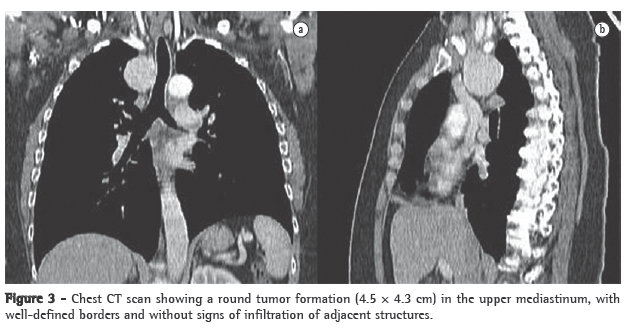

Complementary tests performed in the emergency room revealed normocytic normochromic anemia (hemoglobin, 11.3 mg/dL; mean globular volume, 86.8 fl; and mean corpuscular hemoglobin, 33.7 mg/L), normal total leukocyte counts (7 g/L), hypokalemia (3.3 mmol/L) and hypoalbuminemia (3 g/dL), as well as an increase in the levels of aspartate aminotransferase (60 U/L), alanine aminotransferase (79 U/L), lactate dehydrogenase (196 U/L), alkaline phosphatase (272 U/L) and C-reactive protein (19.2 mg/dL). The patient also presented hypoxemia on room air (PaO2: 79.5 mmHg) and mild hypocapnia (33 mmHg). A chest X-ray revealed opacity in the middle third of the right lung field (Figure 1).

An anteroposterior and lateral right chest X-ray revealed enlargement of the right upper mediastinum.